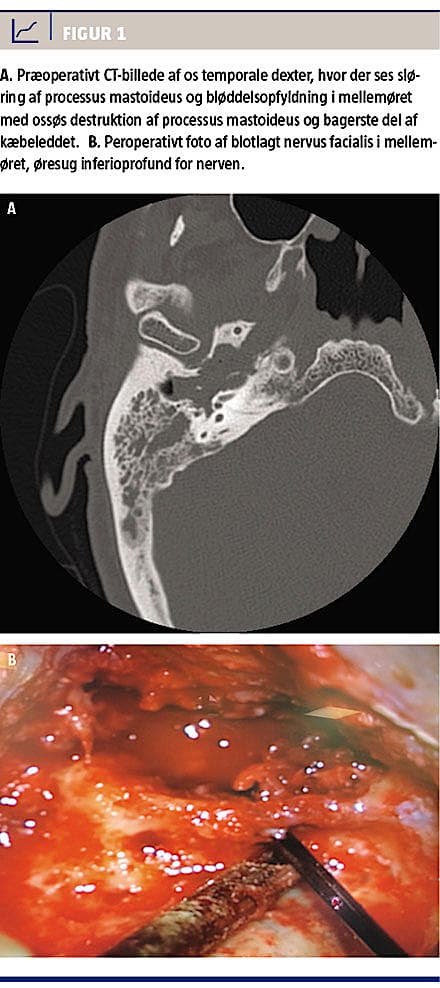

En 72-årig mand, der ikke havde forudgående øreproblematik, blev henvist til et lokalsygehus på grund af højresidig otalgi, øreflåd, intermitterende højresidig perifer facialisparese og reduceret hørelse. Der var ingen svimmelhed eller tinnitus. En initial objektiv undersøgelse viste en polypøs tumor i øregangen ved trommehinden, ingen facialisparese, og en audiometri viste presbyacusis bilateralt samt konduktivt høretab på højre side. En supplerende MR-skanning viste sløring af processus mastoideus og mellemøret på højre side. Initial histologisk undersøgelse af tumoren viste akut og kronisk inflammation samt reaktiv hyperplasi. Videre udredning med CT viste en stor bløddelsopfyldning med knogledestruktion i mellemøret, processus mastoideus, bagerste del af kæbeleddet og basis cranii med blotlæggelse af carotiskanalen (Figur 1A). På mistanke om kolesteatom eller adeno-

Patienten blev derefter henvist til yderligere kirurgisk behandling på Øre-, næse-, halsafdelingen på Rigshospitalet. En præoperativ undersøgelse viste højresidig perifer facialisparese, House-Brackmann grad 3, og en CT viste tumorprogression. Undersø-

Patienten blev senere opereret med højresidig subtotal petrosektomi og blindlukning af øregangen. Peroperativt fandt man tumorvæv i hele mellemøret, processus mastoideus og frem i tubaostiet samt blotlagt dura, arteria carotis interna, vena jugularis interna og nervus facialis, som fremstod ødematøs og misfarvet (Figur 1B). Alt tumorvæv blev fjernet, dog uden garanti for radikalitet mod dura og karskeden. Den endelige histologi viste IP med malign transformation til ikkekeratiniserende planocellulært karcinom. Immunhistokemisk farvning viste P16-over-